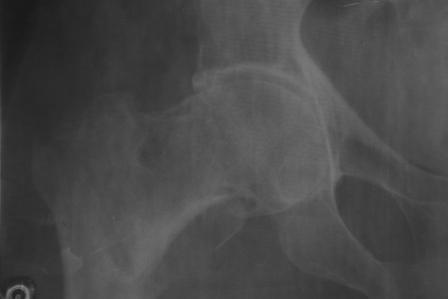

Отправлено Abdurashid Turaev 16 Январь 2008, 18:58

Доставлена больная 72 года. 3 дня назад упала. На R-грамме чрезвертельный простой АО 31А1 перелом левой бедренной кости. Кроме того имеется подозрение на субкапитальный 31В1 перелом , у меня на практике такое впервые. Трижды сделали R-графию, но качественный снимок не получилось. КТ в диагностическом центре на ремонте. 1. Действительно, имеется ли субкапитальный перелом, или мне так кажется? 2. Если да, то что можно делать? В наличии имеется длинные спонгиозные винты, большие расширяюшиеся в конце винты ЦИТО, Г- образные и продольные пластины АО, пластина Троценко-Нуждина, и мыщелковые пластины, заимствованные у Джолдаса. С уважением Абдурашид.

Складывается впечатление о перелома на фоне коксартроза. Соберите получше анамнез ( боли в суставе и т.д.) Мы бы поставили DHS.